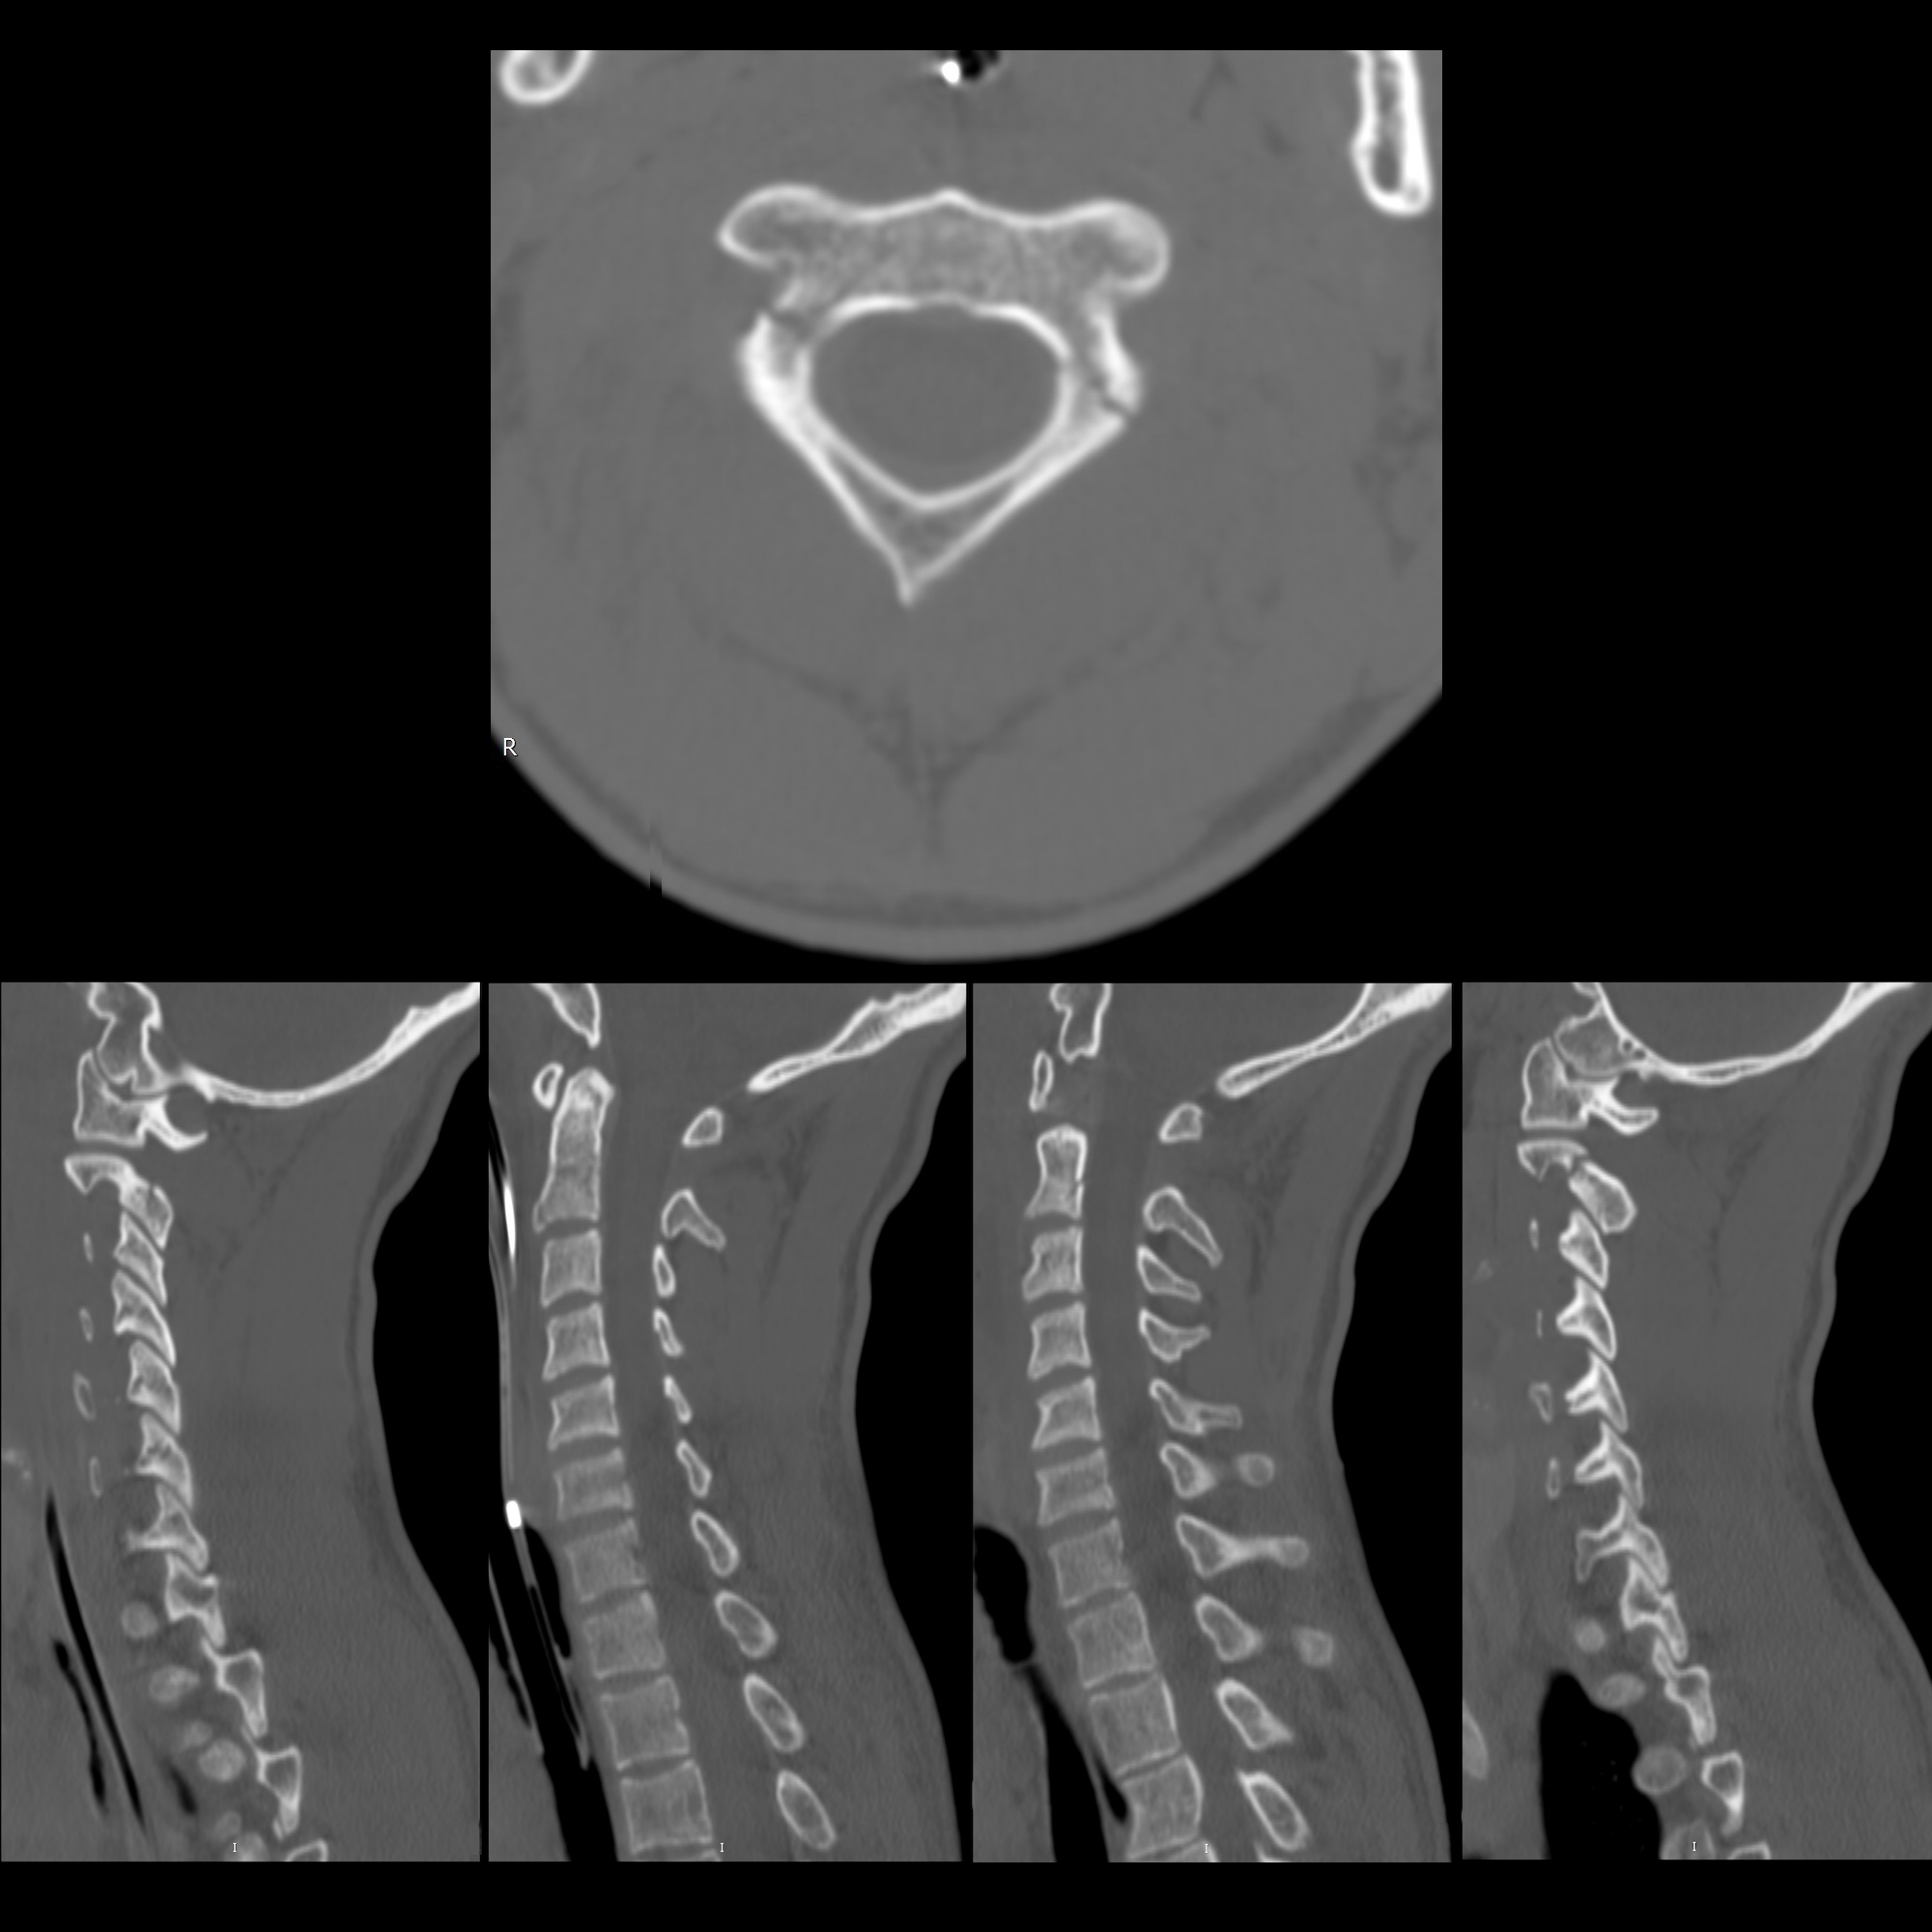

CT appearance of congenital defect resembling the Hangman's fracture, image size:768x1024

CT appearance of congenital defect resembling the Hangman's fracture